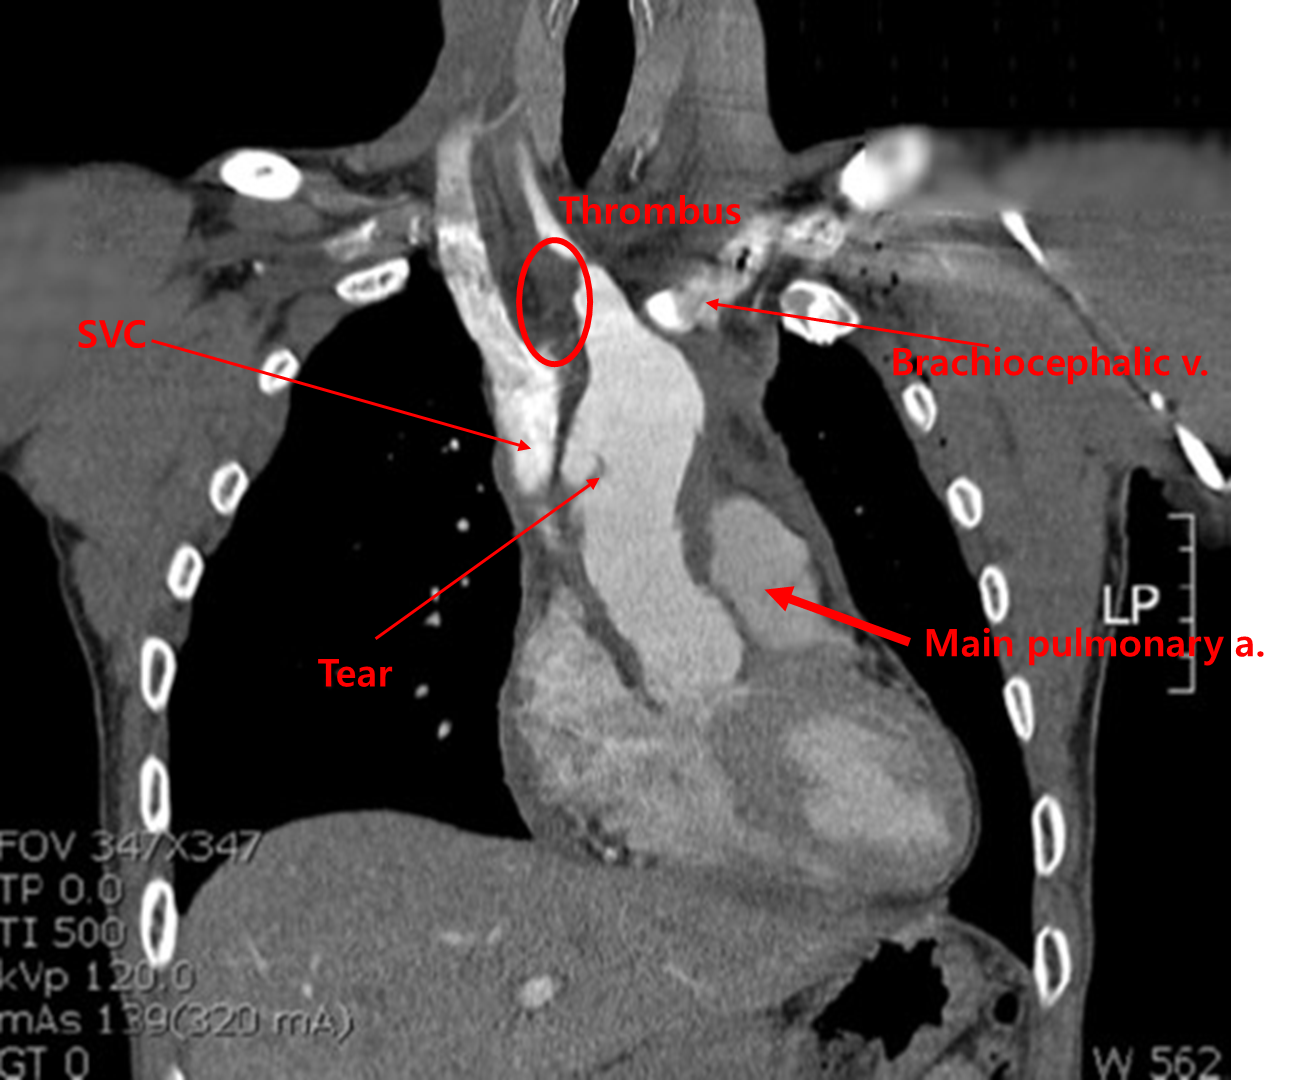

Img | CXR: Cardiomegaly, mediastinal widening CT: Sternum fracture, intimal tear in ascending aorta extending to aortic arch, thrombus in brachiocephalic trunk |

흉부 둔상 후, 양측 사지 혈압 차이가 심하며, CT에서 대동맥 주위 혈종 소견이 보이므로 traumatic thoracic aorta rupture로 진단한다.

• 첫번째 CT에서는 흉부 둔상에 의해 발생한 sternum fracture가 보이며, ascending aorta의 intimal flap도 보인다.

• 두번째 CT에서도 ascending aorta의 intimal flap이 보인다. 해당 부분이 찢어져 내부로 false lumen을 형성하고 brachiocephalic trunk 까지 확장되었고, 이로 인해 우측 상지의 혈압이 낮게 측정되고 있는 것으로 생각된다.

• 따라서 외상에 의해 대동맥의 내막이 파열된 것으로 판단할 수 있으며, 흉부대동맥 파열로 진단한다.